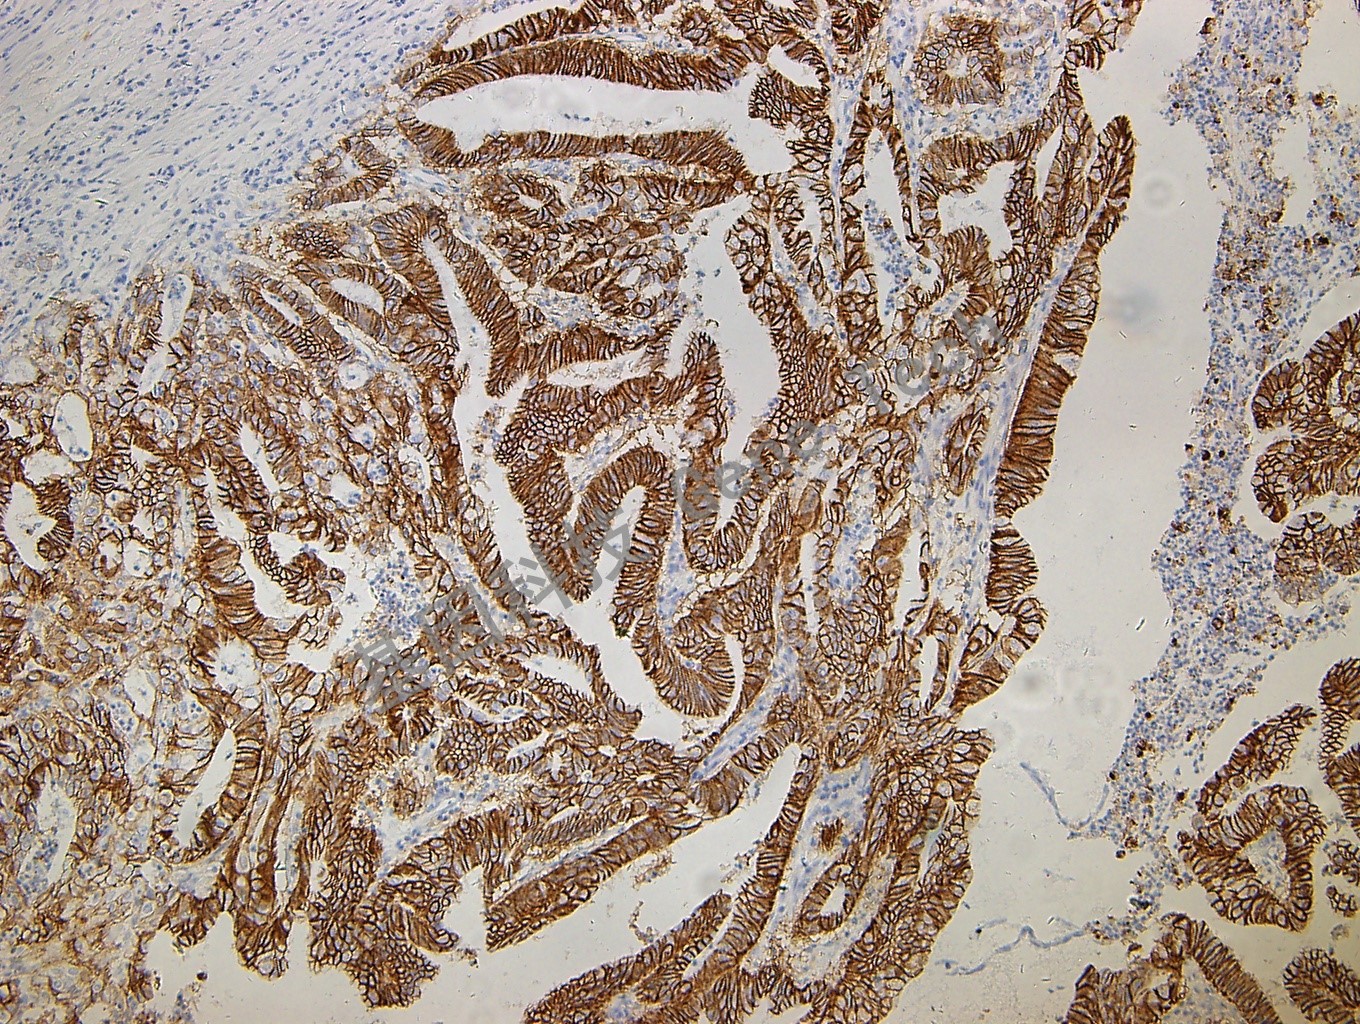

鈣黏附蛋白17(Cadherin17)抗體 鼠抗人 CDH17

| 克隆號:SDM4 | 陽性對照:結(jié)腸癌 | 陽性部位:細胞漿 |

| 預處理:高pH熱修復 | 適用:石蠟切片/冰凍切片 | 顯色系統(tǒng):GTvisionTM |

| 簡介:肝腸- 鈣粘連蛋白(CDH17) 是在小鼠體內(nèi)發(fā)現(xiàn)的一種表達于肝臟和小腸的新型鈣粘連蛋白,在細胞粘附、細胞識別、組織器官的發(fā)育和形態(tài)的維持等方面發(fā)揮重要作用。研究發(fā)現(xiàn)其在多種惡性腫瘤中有高表達,是一種與腫瘤侵襲及轉(zhuǎn)移密切相關的蛋白。目前,CDH17 可作為消化系統(tǒng)腺癌的診斷標記物。 | ||

| 結(jié)腸癌石蠟切片,用 Cadherin 17(GT2208)染色,細胞漿陽性,DAB 顯色。 | ||